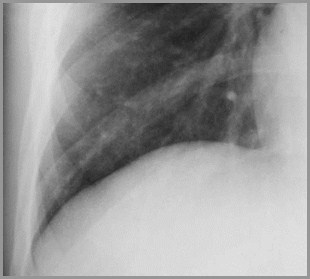

Meniscus Sign

Fluid rises higheralong the edge ofa pleural effusionproducing anupside down “U”or meniscusshape

Meniscus Sign

Pleural fluid tends to rise higher along itsedge producing a meniscus shapemedially and laterally

Usually only lateral meniscus can be seen

The meniscus is a good indicator of thepresence of a pleural effusion